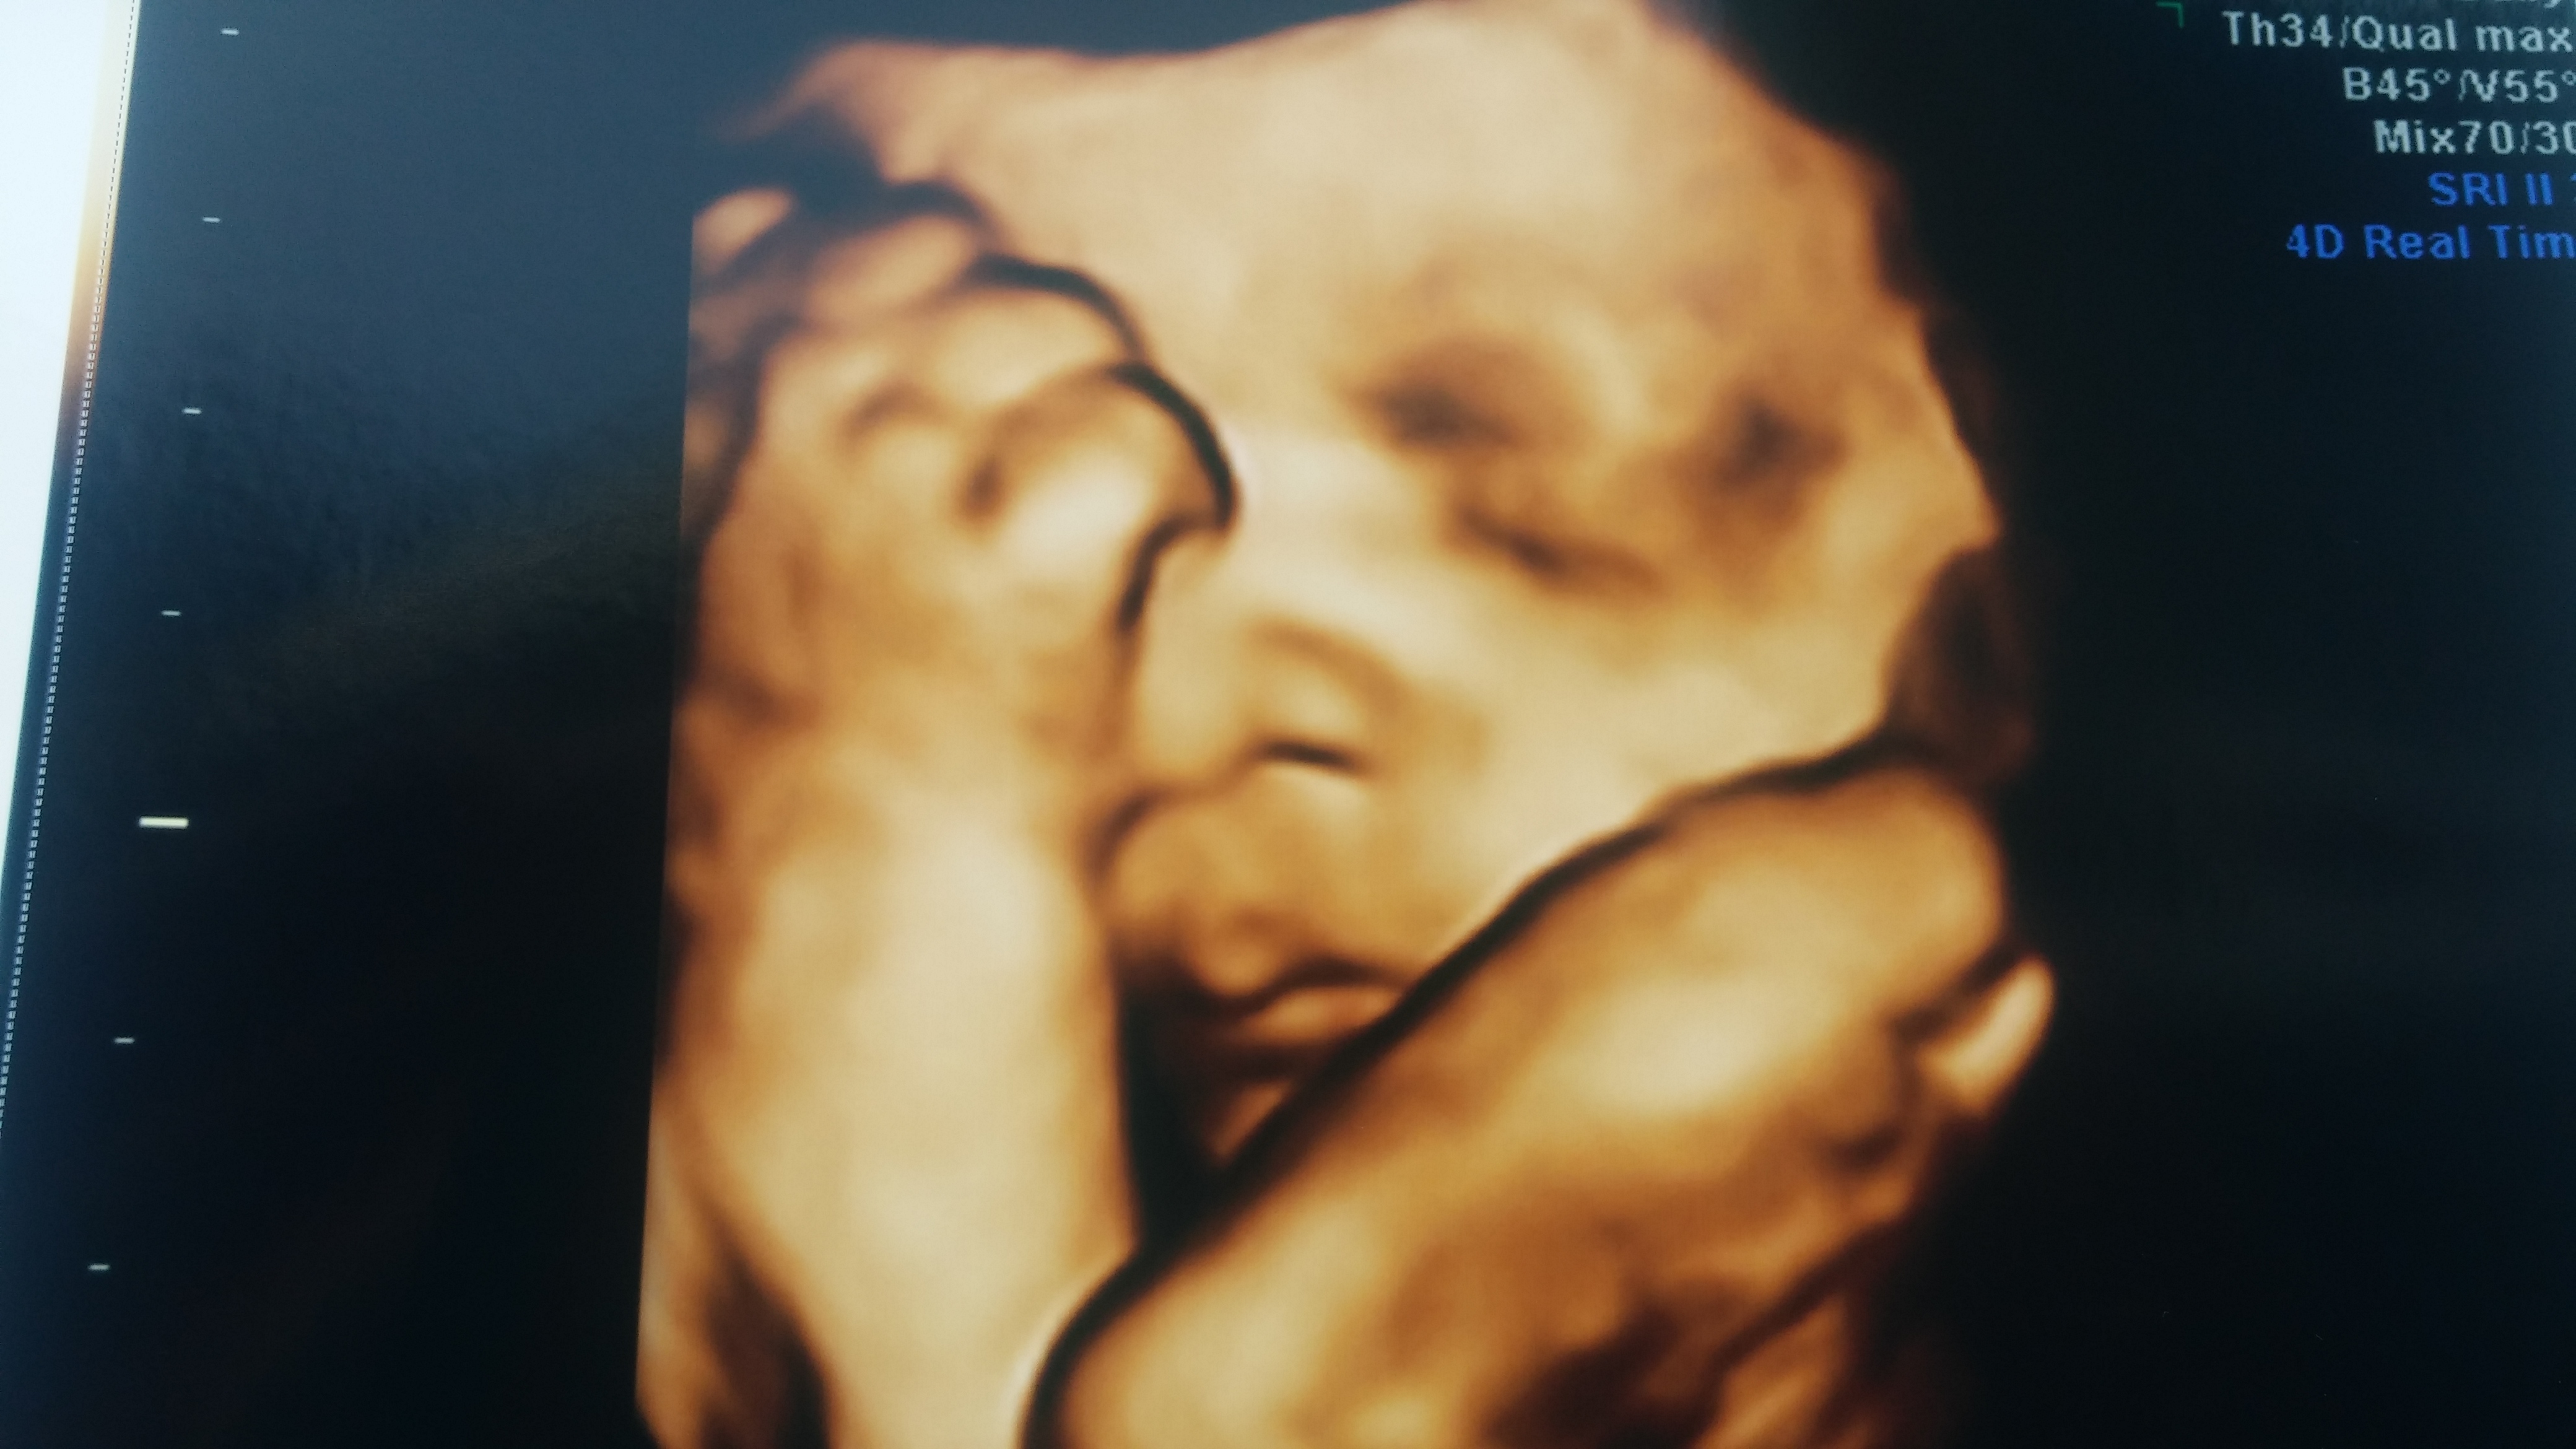

I am so excited that my OB does a 3rd trimester 3D/4D ultrasound. We had one at 15 weeks for gender determination at a place called Peek at me! It was the coolest thing and we got great pictures of him too.

• 32 weeks. She has chubby cheeks